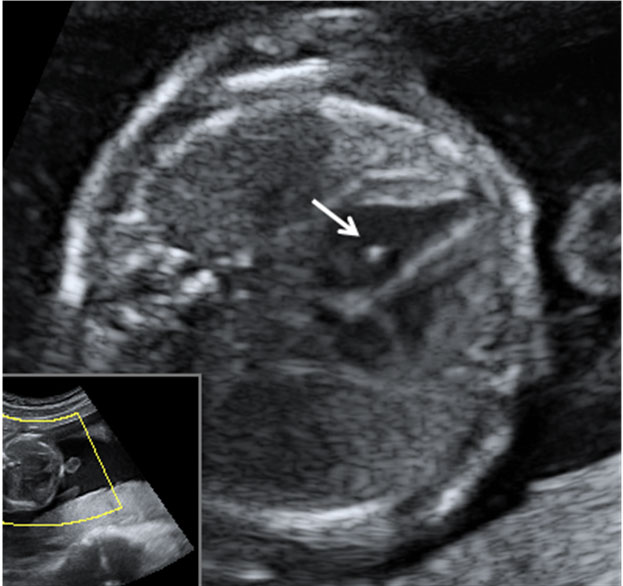

En la ecografía podemos ver una hernia intestinal (u onfalocele), lo que significa que parte del intestino del feto está fuera del abdomen. Observamos la sección transversal del abdomen fetal. A la izquierda, contenido intestinal (entre marcas de medición) herniado fuera del abdomen, debido a un defecto en la inserción del cordón umbilical, que se marca en la imagen con una estrella (*).

Onfalocele o intestino del feto fuera del abdomen